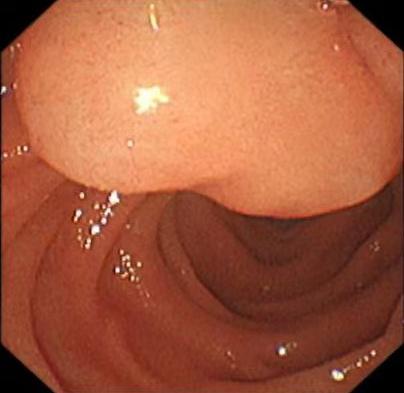

当天,在麻醉科主任医师、医学博士谢文静和副主任医师王冠男的舒适麻醉及内镜中心马瑞卿护士配合下,李振涛操作内镜顺利进入十二指肠降部,发现该部位一巨大黏膜下隆起,同时乳头口白色脓液流出,随乳头插管切开后大量脓液涌出,十二指肠黏膜下隆起迅速消退,胆总管亦清理出一枚成形结石,反复清理胆道确认无结石残留后沿导丝置入一次性胆道子镜,子镜顺利进入胆囊管及胆囊,可见胆囊管及胆囊壁水肿充血明显,腔内大量脓苔、脓液残留,经反复冲洗吸引,患者胆囊高张状态解除,再经内镜中心及麻醉团队娴熟配合,顺利为患者完成ERCP取石及胆囊减压冲洗术,手术全程耗时40分钟,术后当日患者腹痛症状迅速解除,压痛反跳痛症状完全消失。

十二指肠降部脓液积聚